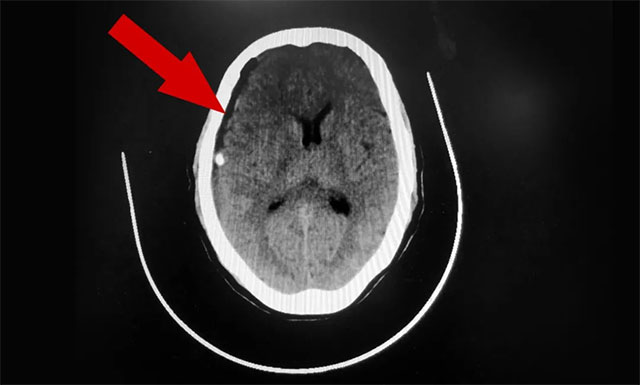

侯增欣主任结合患者病史陈述及影像学检查后诊断为——亚急性硬膜下血肿。当被家人送回上海蓝十字脑科医院并收治于神经外科6A病区后不久,金阿婆便开始出现意识模糊等危重症状况。侯增欣主任团队紧急讨论评估后认为,患者血肿面积较大,且症状不断加重,需立即进行手术治疗。

▲ 术后,患者硬膜下血肿已被引流清除